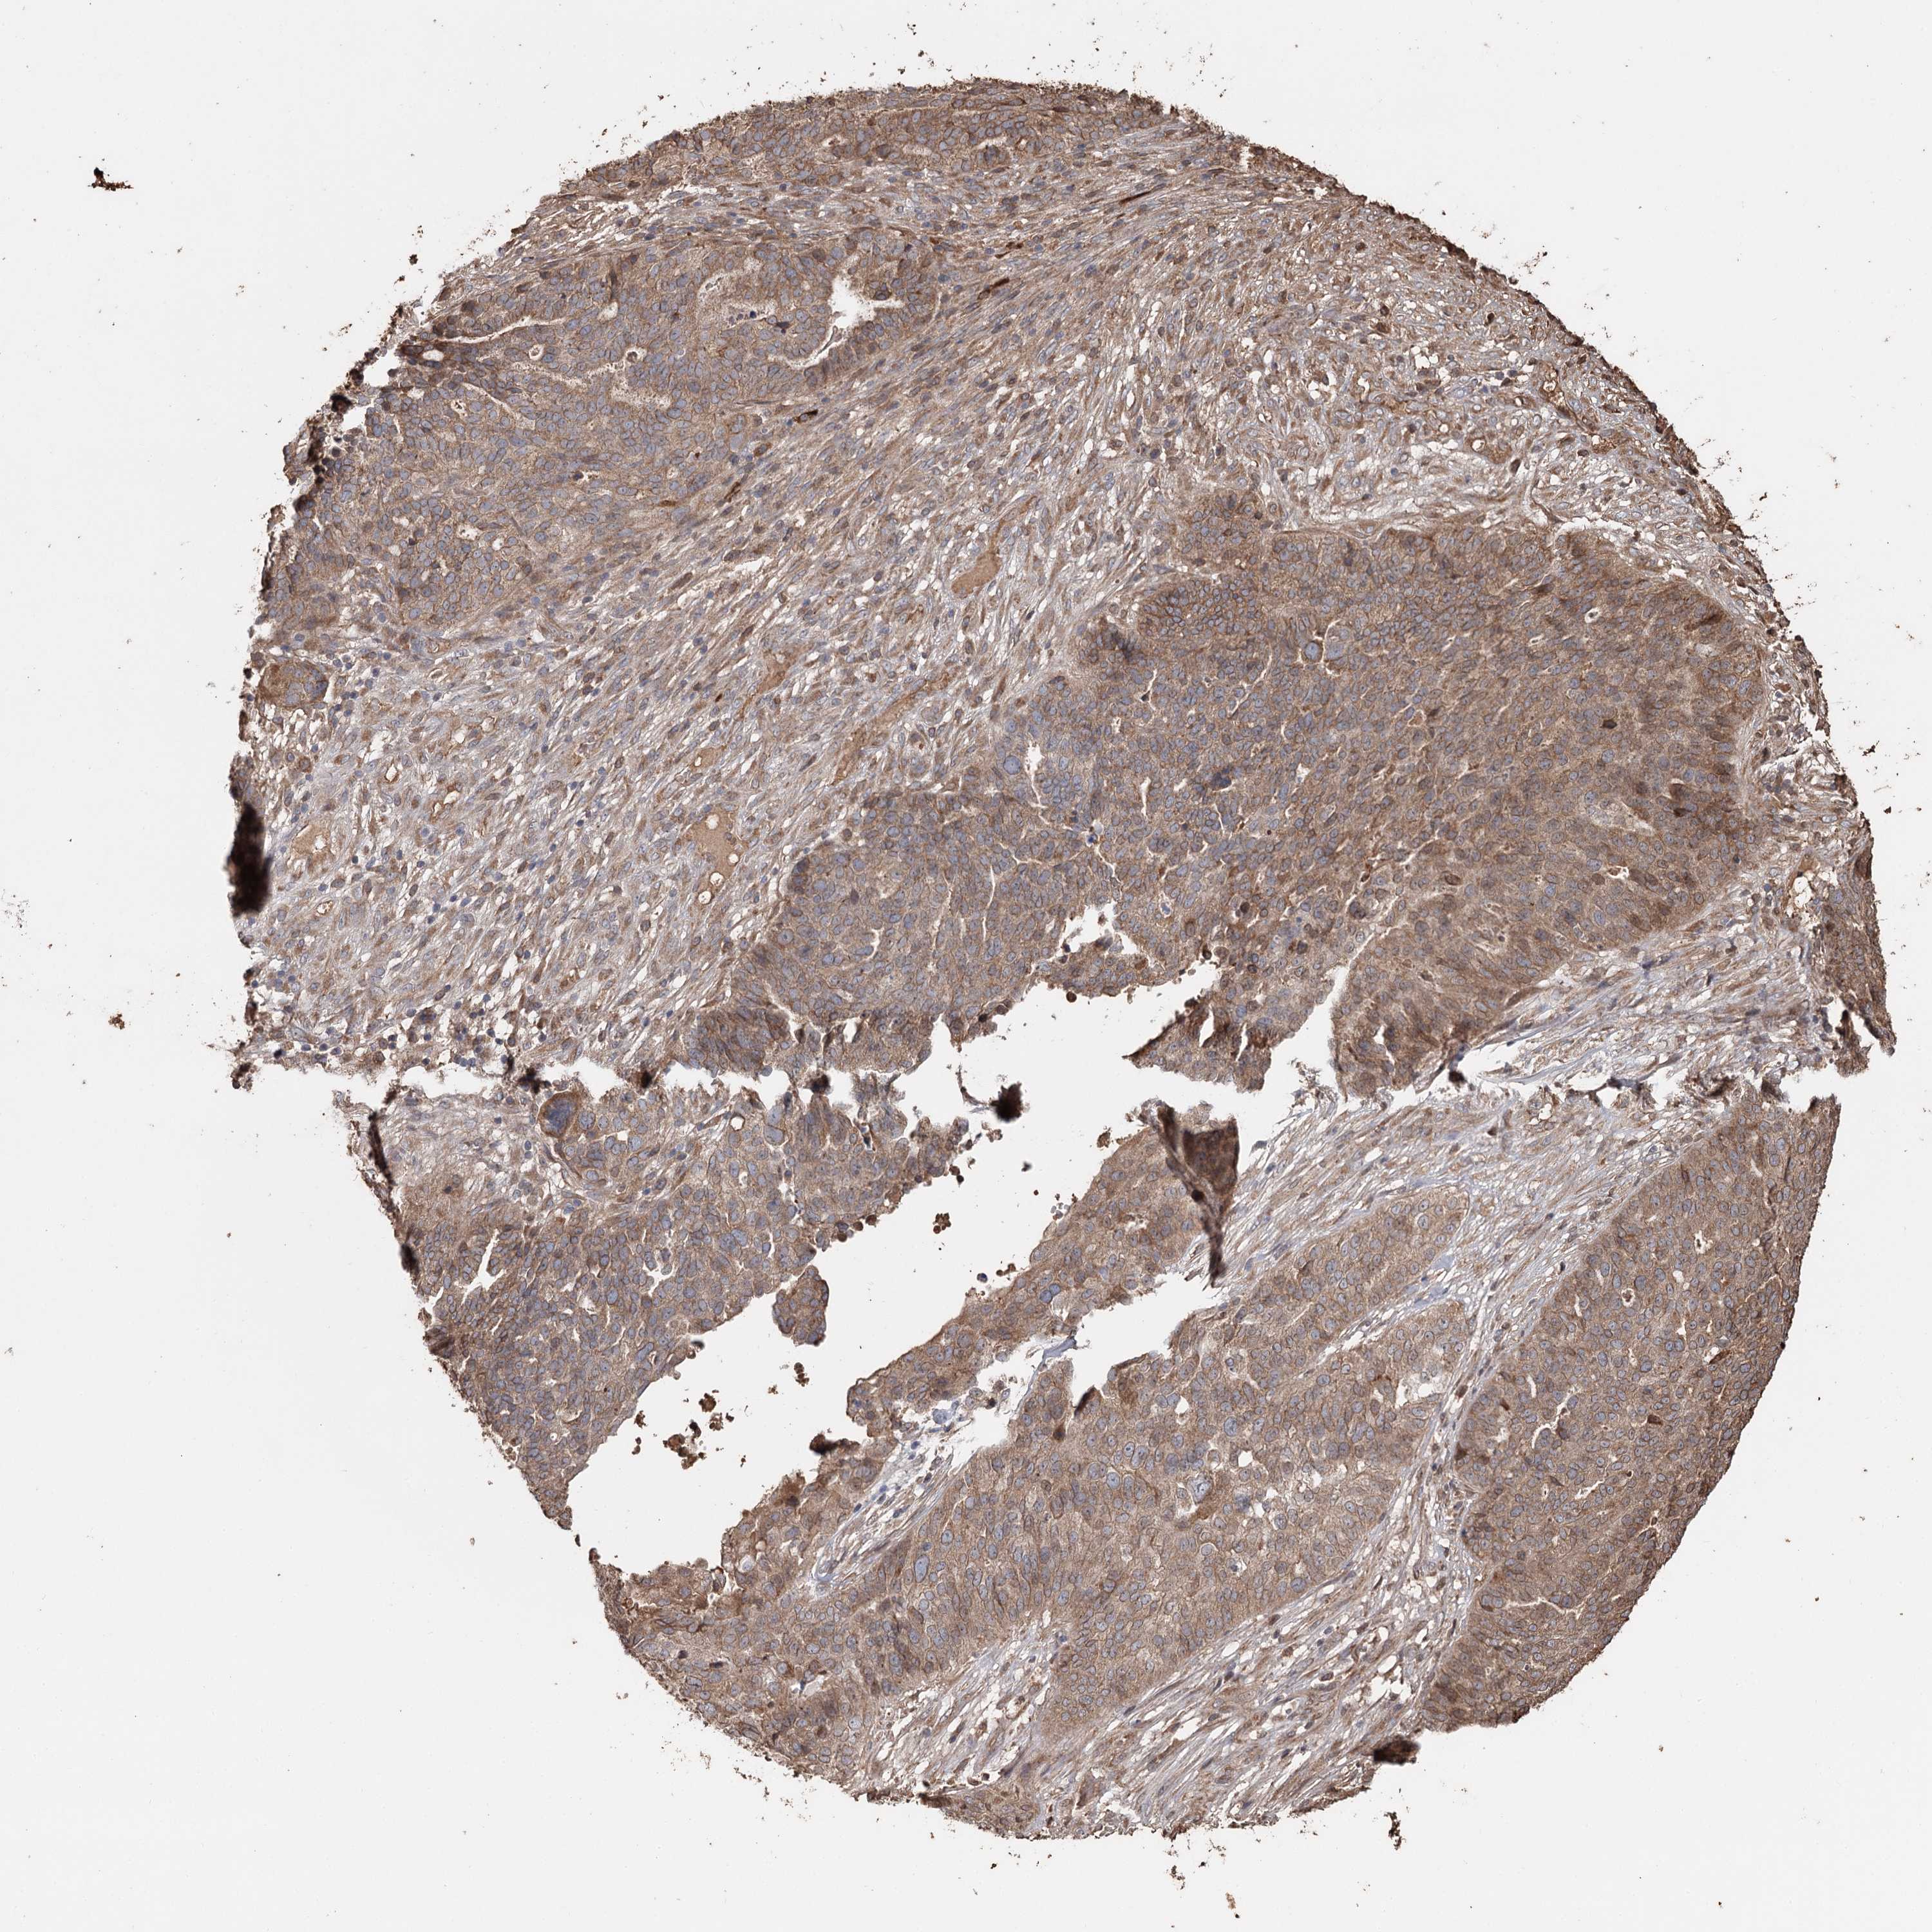

OVARIAN CANCER - Protein expressioni

A mouse-over function shows sample information and annotation data. Click on an image to view it in a full screen mode. Samples can be filtered based on level of antibody staining by selecting one or several of the following categories: high, medium, low and not detected. The assay and annotation is described here.

Note that samples used for immunohistochemistry by the Human Protein Atlas do not correspond to samples in the TCGA dataset.

Antibody stainingi

Antibody staining in the annotated cell types in the current human tissue is reported as not detected, low, medium, or high, based on conventional immunohistochemistry profiling in selected tissues. This score is based on the combination of the staining intensity and fraction of stained cells.

Each image is clickable and will lead to virtual microscopy that enables deeper exploration of all samples and also displays staining intensity scores, fraction scores and subcellular localization as well as patient and tissue information for each sample.

Antibody HPA005480

Antibody HPA024300

Antibody CAB037030

Cystadenocarcinoma, serous, NOS

Carcinoma, endometroid

Carcinoma, NOS

Cystadenocarcinoma, mucinous, NOS